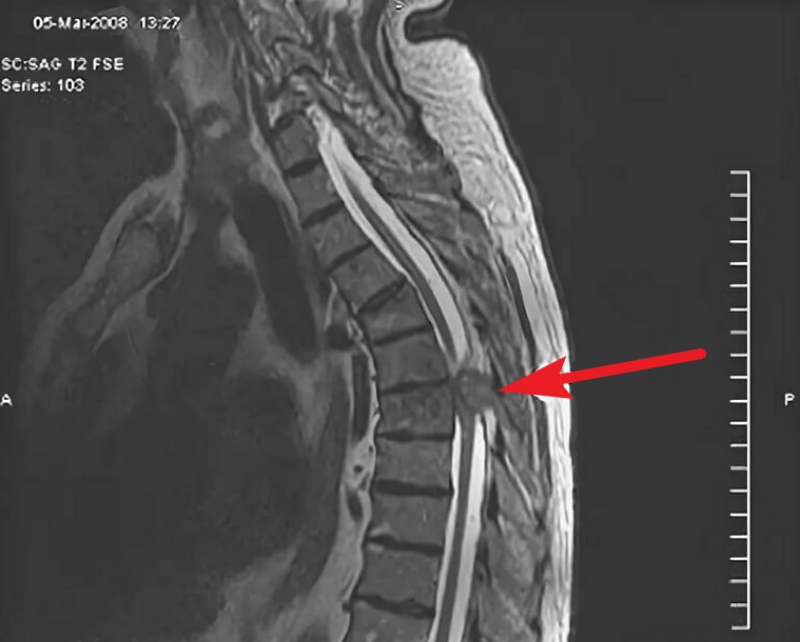

Результаты миелографии представляют собой серию детализированных снимков, на которых видно распределение контрастного вещества в позвоночном канале. Анализируя эти изображения, врач-рентгенолог может выявить различные патологии. Например, сужение или полная блокада (стоп-контраст) на определенном уровне указывает на сдавление спинного мозга грыжей, опухолью или костными разрастаниями. Деформация контуров дурального мешка или нервных корешков также является важным диагностическим признаком.